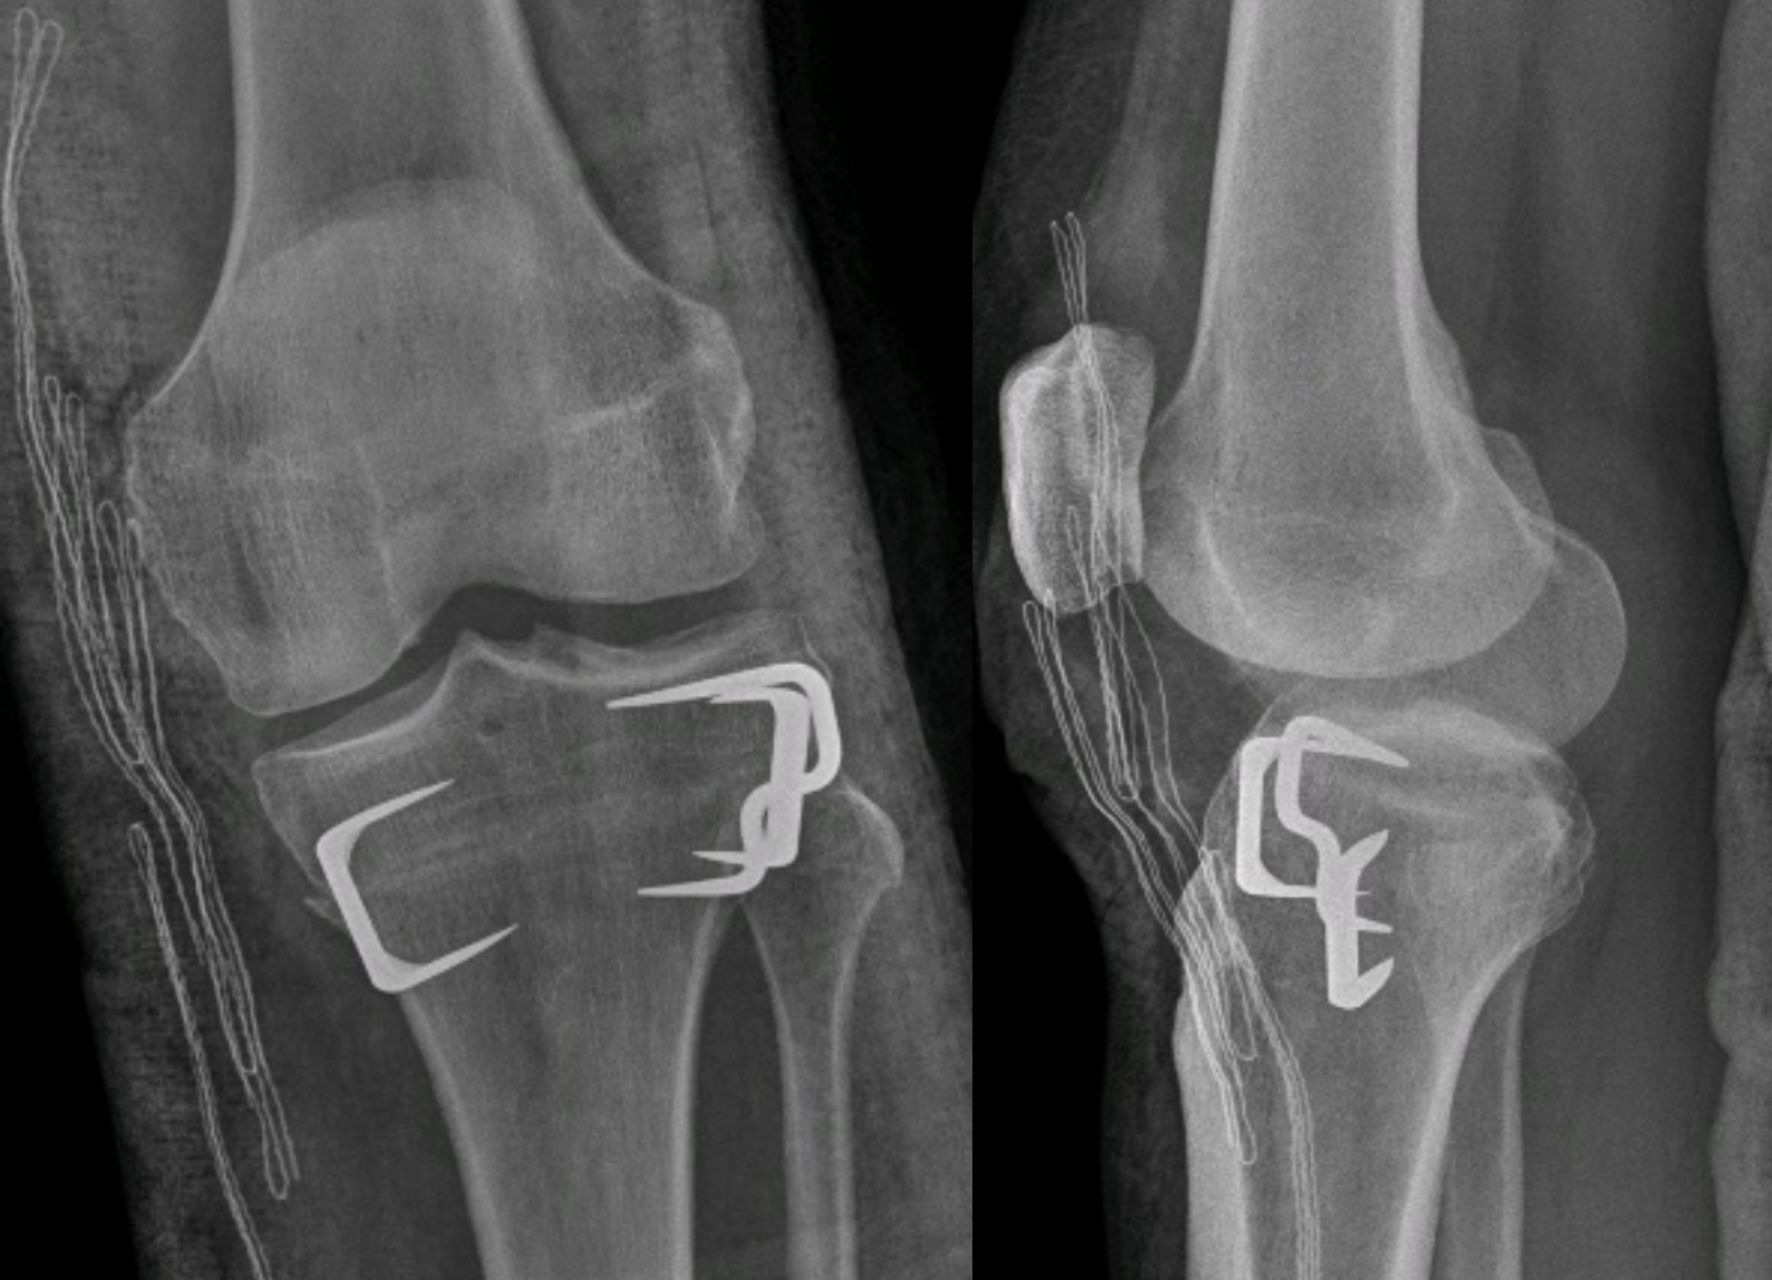

Fixation Method

Once the derotation is achieved, the tibia must be fixed in the new position. This can be done with specifically designed plates and screws, or with staples. This decision will be left to surgeon's preference. Plating has the advantage of more theoretical stability. However, its drawbacks include losing some degree of correction while plating (longer time screwing), longer procedure time, need of hardware removal, longer incision, and a higher cost. It is likely more suitable for tridimensional osteotomies (correction of valgus and torsion) where a more rigid fixation is required (Figure 12).

In isolated supratuberositary osteotomies, lateral compression staples are usually enough for a correct fixation. It reduces the operating time and maintains the correction of the torsion quickly when obtained, while also being less irritating for soft tissues than a plate. The use of two staples is recommended. The first staple is inserted from lateral to medial (Figure 13), and the second staple can be inserted in the same manner or, if possible, from anterior to posterior, perpendicular to the other to prevent loss of rotation (Figure 14). In some cases of medial opening after fixation, a further staple can be added on the medial side with a small incision (Figure 15). However, this is not advised as the medial staples can be highly irritating.